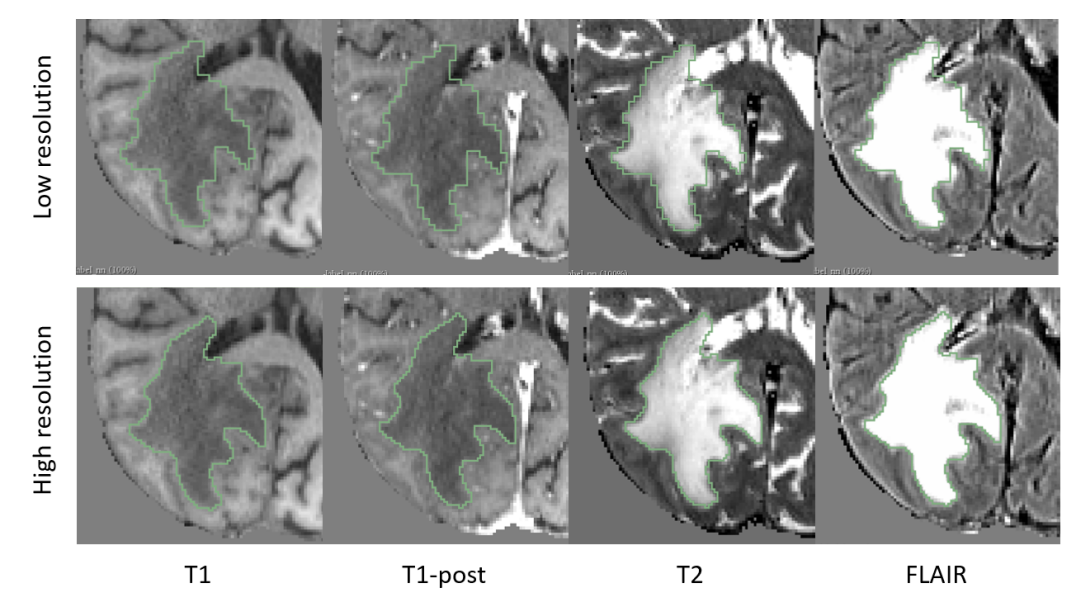

Figures 2 and 3 shows example segmentation results for whole tumor, enhancing tumor and tumor core. Results over the BraTS validation set are shown in Figure 4. These results reflect those reported via the online leaderboard on 8th September 2017 444https://www.cbica.upenn.edu/BraTS17/lboardValidation.html. Out of the 61 entrants, our algorithm places 21st for whole tumor, 16th for enhancing tumor and 28th for tumor core.

Refer to caption

Figure 2: Example segmentation result for whole tumor. Low resolution (top) labelmaps are upsampled using nearest-neighbour interpolation, and upsampled to high resolution (bottom).